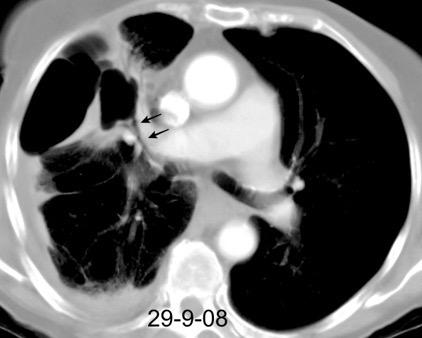

Marzo 2014: Perforación longitudinal distal secundaria a episodio de vómito (síndrome de Boerhaave). Derrame pleural izdo. que evoluciona a empiema.

Wang C-T et al. Tension hydropneumothorax in a Boerhaave syndrome patient: A case report . World J Emerg Med, 2021. Katabathina V et al. Nonvascular, nontraumatic mediastinal emergencies in adults:a comprehensive review of imaging findings. Radiographics. 2011.